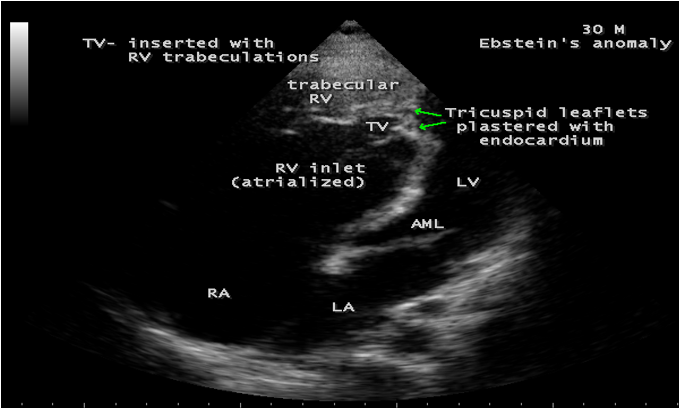

A 30-year old male was presented with marked cyanosis and no murmur and abnormal heart sounds on auscultation. 2D echocardiography revealed the features of Ebstein’s anomaly such as insertion of anterior leaflet into the trabeculated RV, forming a ‘blanket’ of leaflet tissue across the inflow and trabecular parts and bulging of ventricular septum towards leftward due to marked dilatation of RV, and LV became ‘banana’ shaped as shown in Figures 28 to 30.

Echocardiographic features Echocardiography is the diagnostic test of choice for Ebstein’s anomaly and the first echocardiographic diagnosis was reported by Lundstrom in 1969. The first diagnostic criteria for Ebstein’s anomaly using a multi-crystal two-dimensional system was defined by Hagan in 1974 [33] and they were able to recognize the apical displacement of the septal tricuspid leaflet and an elongated anterior tricuspid leaflet with increased excursion. The septal leaflet of the tricuspid valve attaches chiefly to the ventricular septum , but part of its basal attachment is to the posterior wall of the right ventricle [34] and it normally exhibits a slight but distinct apical displacement of its basal attachment to the central fibrous body compared to the mitral valve. The distal displacement of septal origin of tricuspid valve seems to be the best echocardiographic criterion as the characteristic sign for Ebstein’s anomaly and the degree of maximal displacement in normal hearts varies considerably with a mean difference of approximately 6 mm with mitral valve. To define the anatomic severity of Ebstein’s anomaly, four-chamber view is the best to demonstrate the apical displacement of septal tricuspid leaflet [35]. The ratio between the mitral-to-apex distance and the tricuspid-to-apex distance varies from 1 to 1.2 in normal subjects and 1.8 to 3.2 in patients and it is 3.6 as in Figure 18 with Ebstein’s anomaly. The true distance in the level of insertion of atrioventricular valves is obtained by substracting the tricuspid-to-apex distance from the mitral-to-apex distance with a mean value of 27.25 ± 12 mm in patients with proven Ebstein’s anomaly and it is 60 mm as shown in Figure 18 compared to reference group (5.7 ± 2 mm). Kambe and coworkers calculated the distance between both atrioventricular valves directly as a mean value of 21 mm with a range of 14 to 32 mm [36]. A maximum difference in the level of valve insertion of >15 mm in children and >20 mm in adults is discriminated between normal and Ebstein’s anomaly [37],[38]. Despite this fact, a patient with an ‘unequivocal’ Ebstein’s malformation can be encountered in whom the diagnosis cannot be made with certainity solely on the basis of apical displacement of the septal tricuspid valve leaflet. Occasionally, the leaflet attaches to the trabecular part rather than the inlet part of the septum, the conventional four-chamber view will not reveal any septal insertion as shown in Figures 28 and 29.

The anterior tricuspid leaflet is not involved in the process of downward displacement, it may be abnormally inserted occasionally and Shiina, et al documented the apical displacement of anterior tricuspid leaflet in 14% of cases echocardiographically [39]. The anterior leaflet forms a large, sail-like intracavitary curtain as in Figures 14, 25 and contains muscular strands instead of consisting entirely of a fibrous membrane as in the normal tricuspid valve [40]. It is potentially mobile with a brisk sail-like movement as shown in Figure 21 to 24 [41], free bloating with a ‘whipping motion’ across the right ventricular outflow tract (RVOT) as shown in Figure 26 and in some cases, the movement is restricted due to its adherence to the ventricular wall as in Figure 1 and 2, 4 and 9. It is often fenestrated, may in part be musculaized , inserting into the trabeculations of the right ventricle (RV) as in Figure 28 and rarely, the anterior leaflet forms an ‘atretic’ membrane that spans the midportion of the right ventricular cavity as in Figure 16.

In severe cases, the inferior wall of the right ventricle may consists soley of thin fibrous tissue, devoid of myocytes and thereby represent an area of aneurysmal dilatation as in Cases 2 (Figure 8) and 3 (Figures 20 and 24). It is apparently due either to slippage of right ventricular inflow tract away from the right atrioventricular junction or to focal excessive ‘undermining’ to myocardium, transmurally to the level of epicardium. A large atrialized area causes a severe reduction in the volume of the right ventricular pumping chamber and usually produces an abnormal configuration of muscular interventricular septum, which bulges leftward and thereby compresses the left ventricular chamber, resulting in reversal of ventricular shapes with a ‘circular’ right ventricle and a ‘banana’ [42] or ‘crescentic’ [43] left ventricle as shown in Figures 29 and 30 Thus, the proximal component of the right ventricle, the ‘inlet portion’ is the part directly involved with the malformation and the distal apico-trabecular and outlet portions that constitute the ‘functional right ventricle’, which is not involved and may be of normal size, but usually markedly diminished in dimensions and in some cases, it is dilated and thin walled.